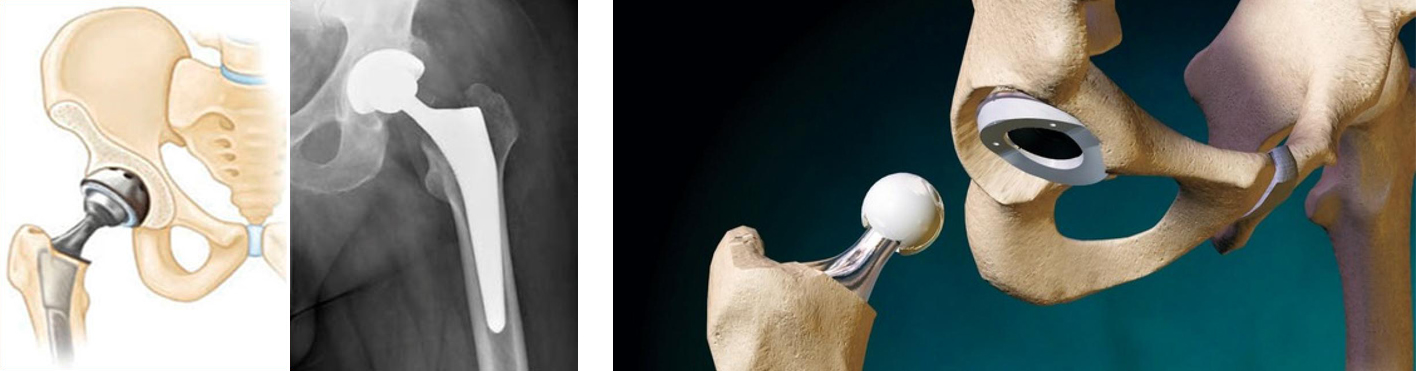

Диагностика ТБС рентгеном и асептический некроз: особенности лечения

Раздел: Снимки-откровения